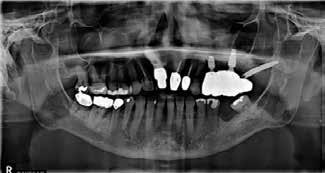

#13, #14 for ridge preservation. At a later date, three implant-supported crowns in close proximity were placed in these sites. Notably, the crowns were non-splinted. (Fig. 1).

In July 2021, the patient presented with mobile implants #12, #13 and #14 to his dental practitioner (Fig. 2). The implants were removed without bone grafting.

Fig. 1: May 2021. Panoramic radiograph shortly after placement of upper left #12, #13, #14.